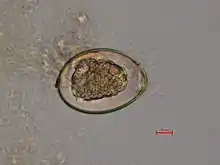

The adult worm is composed of three fairly distinct morphological segments: the scolex (head), the neck, and the lower body. Each side of the scolex has a slit-like groove, which is a bothrium for attachment to the intestine. The scolex attaches to the neck, or proliferative region. From the neck grow many proglottid segments which contain the reproductive organs of the worm. D. latum is the longest tapeworm in humans, averaging ten meters long. Unlike many other tapeworms, Diphyllobothrium eggs are typically unembryonated when passed in human feces.[4]

Because humans do not generally eat undercooked minnows and similar small freshwater fish, these do not represent an important source of infection. Nevertheless, these small second intermediate hosts can be eaten by larger predator species, for example trout, perch, walleye, and pike. In this case, the sparganum can migrate to the musculature of the larger predator fish and mammals can acquire the disease by eating these later intermediate infected host fish raw or undercooked. After ingestion of the infected fish, the plerocercoids develop into immature adults and then into mature adult tapeworms which will reside in the small intestine. The adults attach to the intestinal mucosa by means of the two bilateral grooves (bothria) of their scolices. The adults can reach more than 10 m (up to 30 ft) in length in some species such as D. latum, with more than 3,000 proglottids. One or several of the tape-like proglottid segments (hence the name tapeworm) regularly detach from the main body of the worm and release immature eggs in freshwater to start the cycle over again. Immature eggs are discharged from the proglottids (up to 1,000,000 eggs per day per worm) and are passed in the feces. The incubation period in humans, after which eggs begin to appear in the feces is typically 4–6 weeks, but can vary from as short as 2 weeks to as long as 2 years.[7]